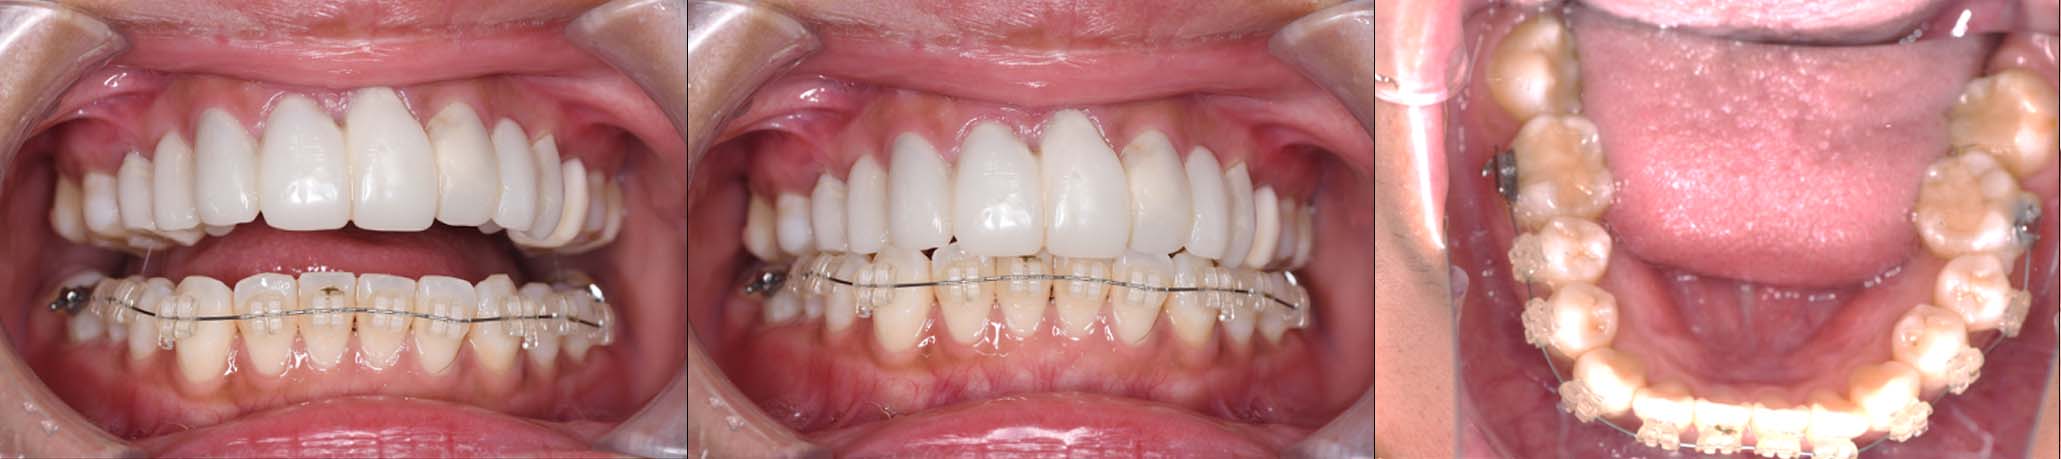

2024年 10月 下顎MTM開始

2024年 10月10日

10月21日

11月7日

11月28日